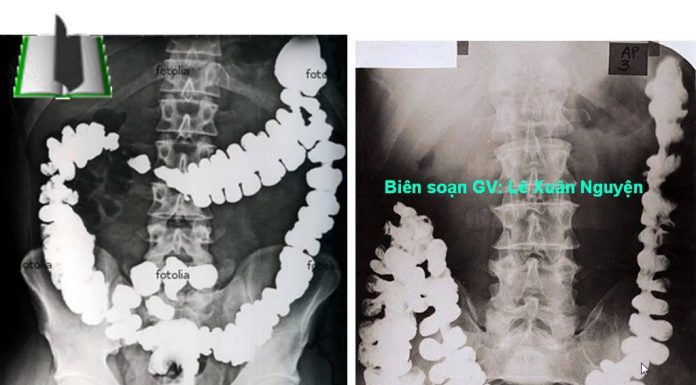

Thăm dò hình thái đường tiêu hóa bằng siêu âm qua thành bụng

Siêu âm qua thành bụng (Ultrasound - US)

Trước đây siêu âm được dùng cho chẩn đoán bệnh lý gan, mật, tụy, lách, thận và...